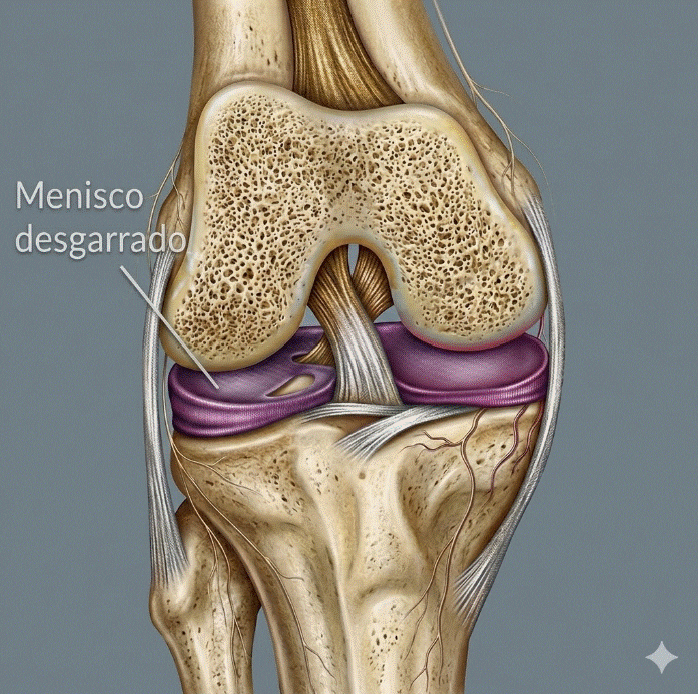

Tendinopatía rotuliana en deportistas: tratamiento y evidencia

La tendinopatía rotuliana en deportistas es una de las lesiones por sobrecarga más frecuentes y limitantes en los deportes que implican saltos repetitivos, como el baloncesto, el voleibol, el atletismo de saltos o el fútbol. Conocida popularmente como «rodilla del saltador», esta patología afecta al tendón rotuliano en su inserción en el polo inferior de […]